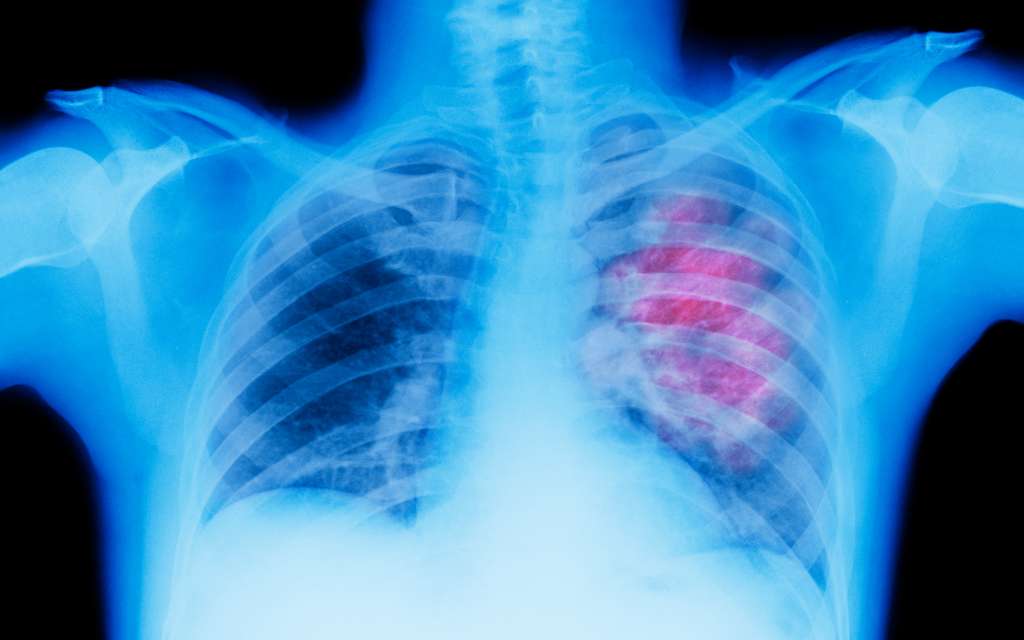

Deaths from lung cancer and melanoma saw “accelerated” declines compared to other cancers. Researchers said the drop in lung cancer death rates drove the overall decline, and the melanoma decline represented a “substantial increase in survival for metastatic melanoma.”

“The declines in lung cancer and melanoma death rates are the result of progress across the entire cancer continuum – from reduced smoking rates to prevent cancer to discoveries such as targeted drug therapies and immune checkpoint inhibitors,” Karen Knudsen, chief executive officer of the American Cancer Society, said in a news release.